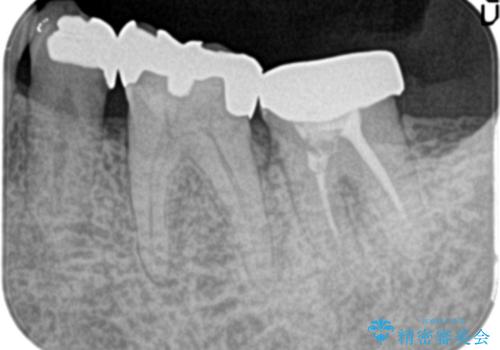

- 他院で治療したが、痛みが続いていることを主訴に来院されました。

痛みの原因歯を特定し、根管治療を行い、オールセラミッククラウンにて咬合回復しております。

根管治療は林先生に依頼しております。

根管治療後、精度の高い被せ物を入れることは歯の予後に大きく関わります。